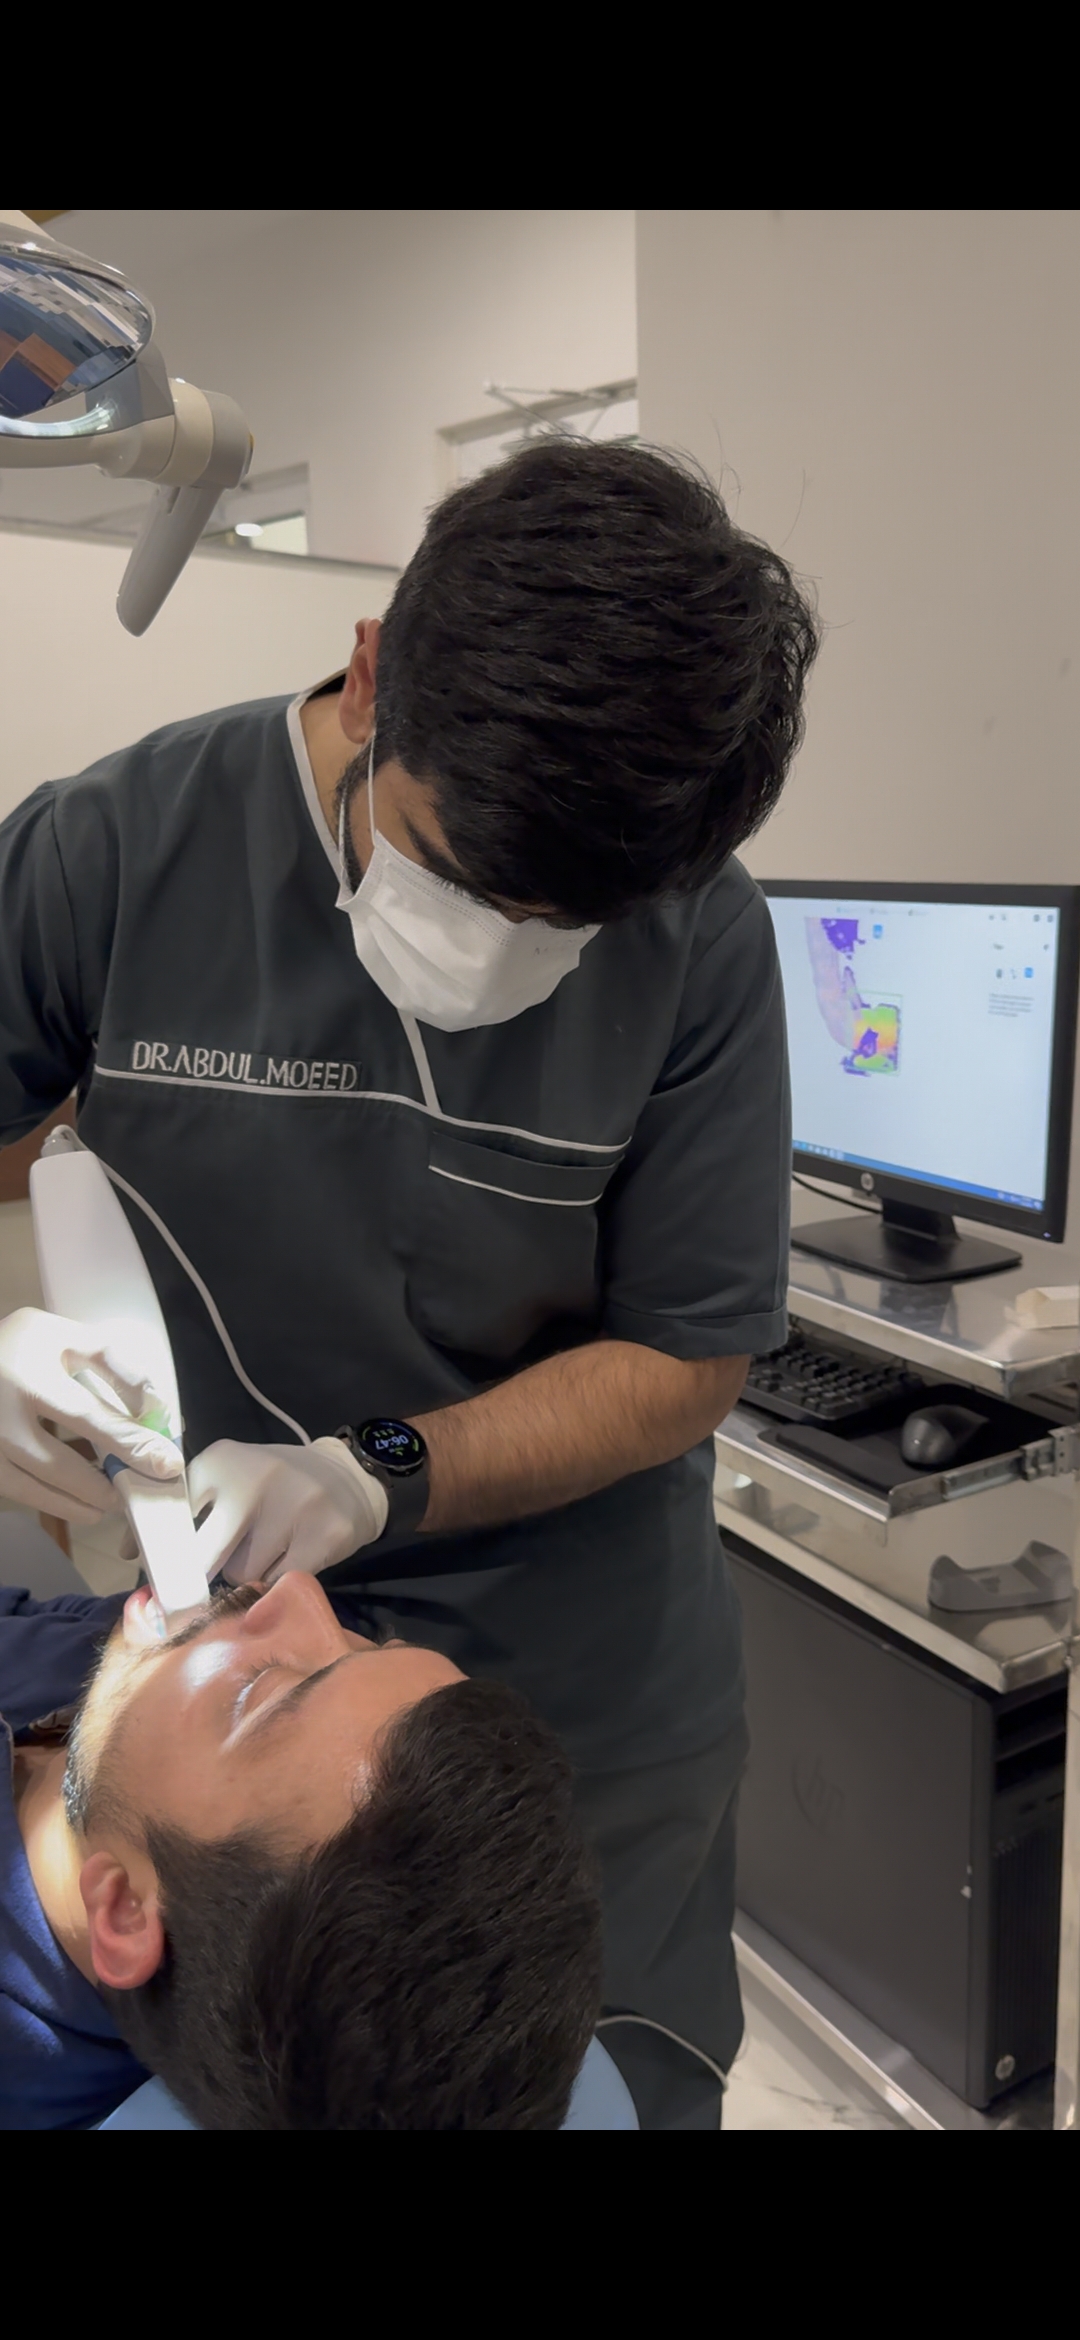

Intra Oral Scanning

Get Digital Impressions for your Prosthesis (Crowns, Bridges, Dentures and others) For maximum accuracy and no loss of Data